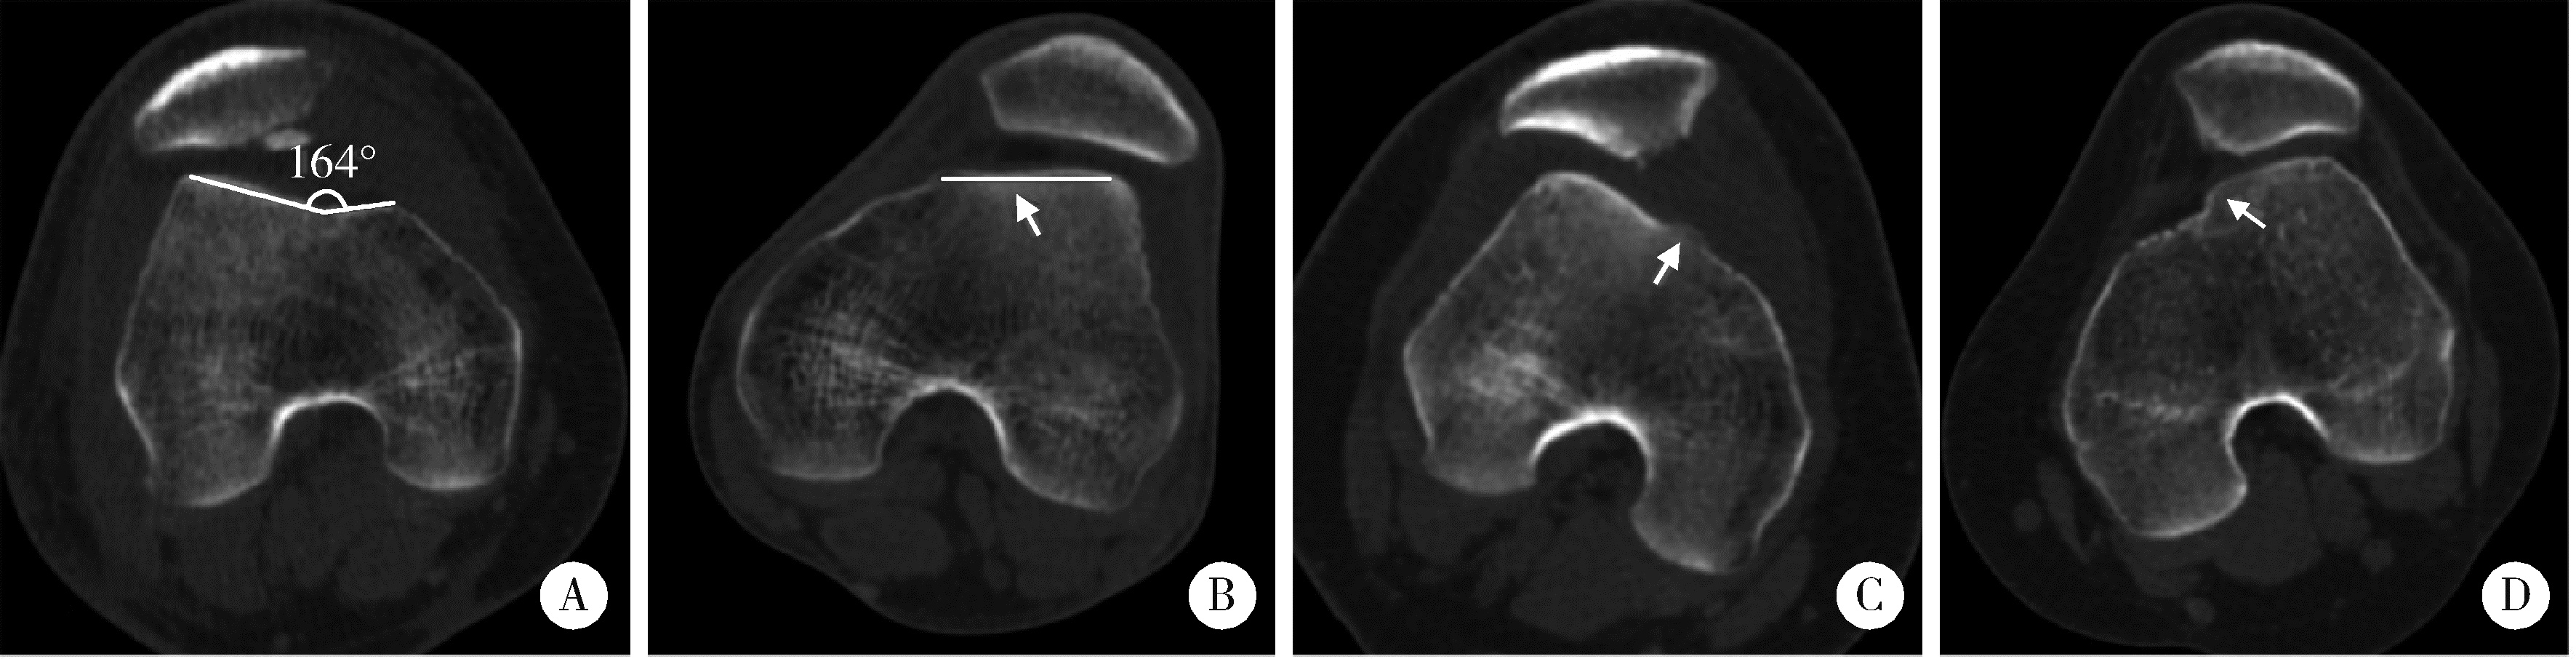

Figure 3

Measurements of radiographic parameters on lateral plain radiographs and axial CT A, Insall-Salvati index is the ratio of the patellar tendon length (T) to the patellar height (P1, distance from the superior pole to the inferior pole) on lateral plain radiographs; B, TT-TG distance is calculated by the transverse length between the trochlear groove and the tibial tuberosity on axial images; C, PT is the angle between the transverse axis of the patella and the posterior femoral condylar line; D, LPD describes the distance between the medial margin of the patella and the medial trochlear margin measured by lines perpendicular to the posterior femoral condylar line; E, bisect offset is determined by the ratio at which the patella width was bisected from its lateral aspect to the transverse width of the patella (L/P2). CT, computed tomography; LPD, lateral patellar displacement; PT, patellar tilt; TT-TG, tibial tubercle-trochlear groove."